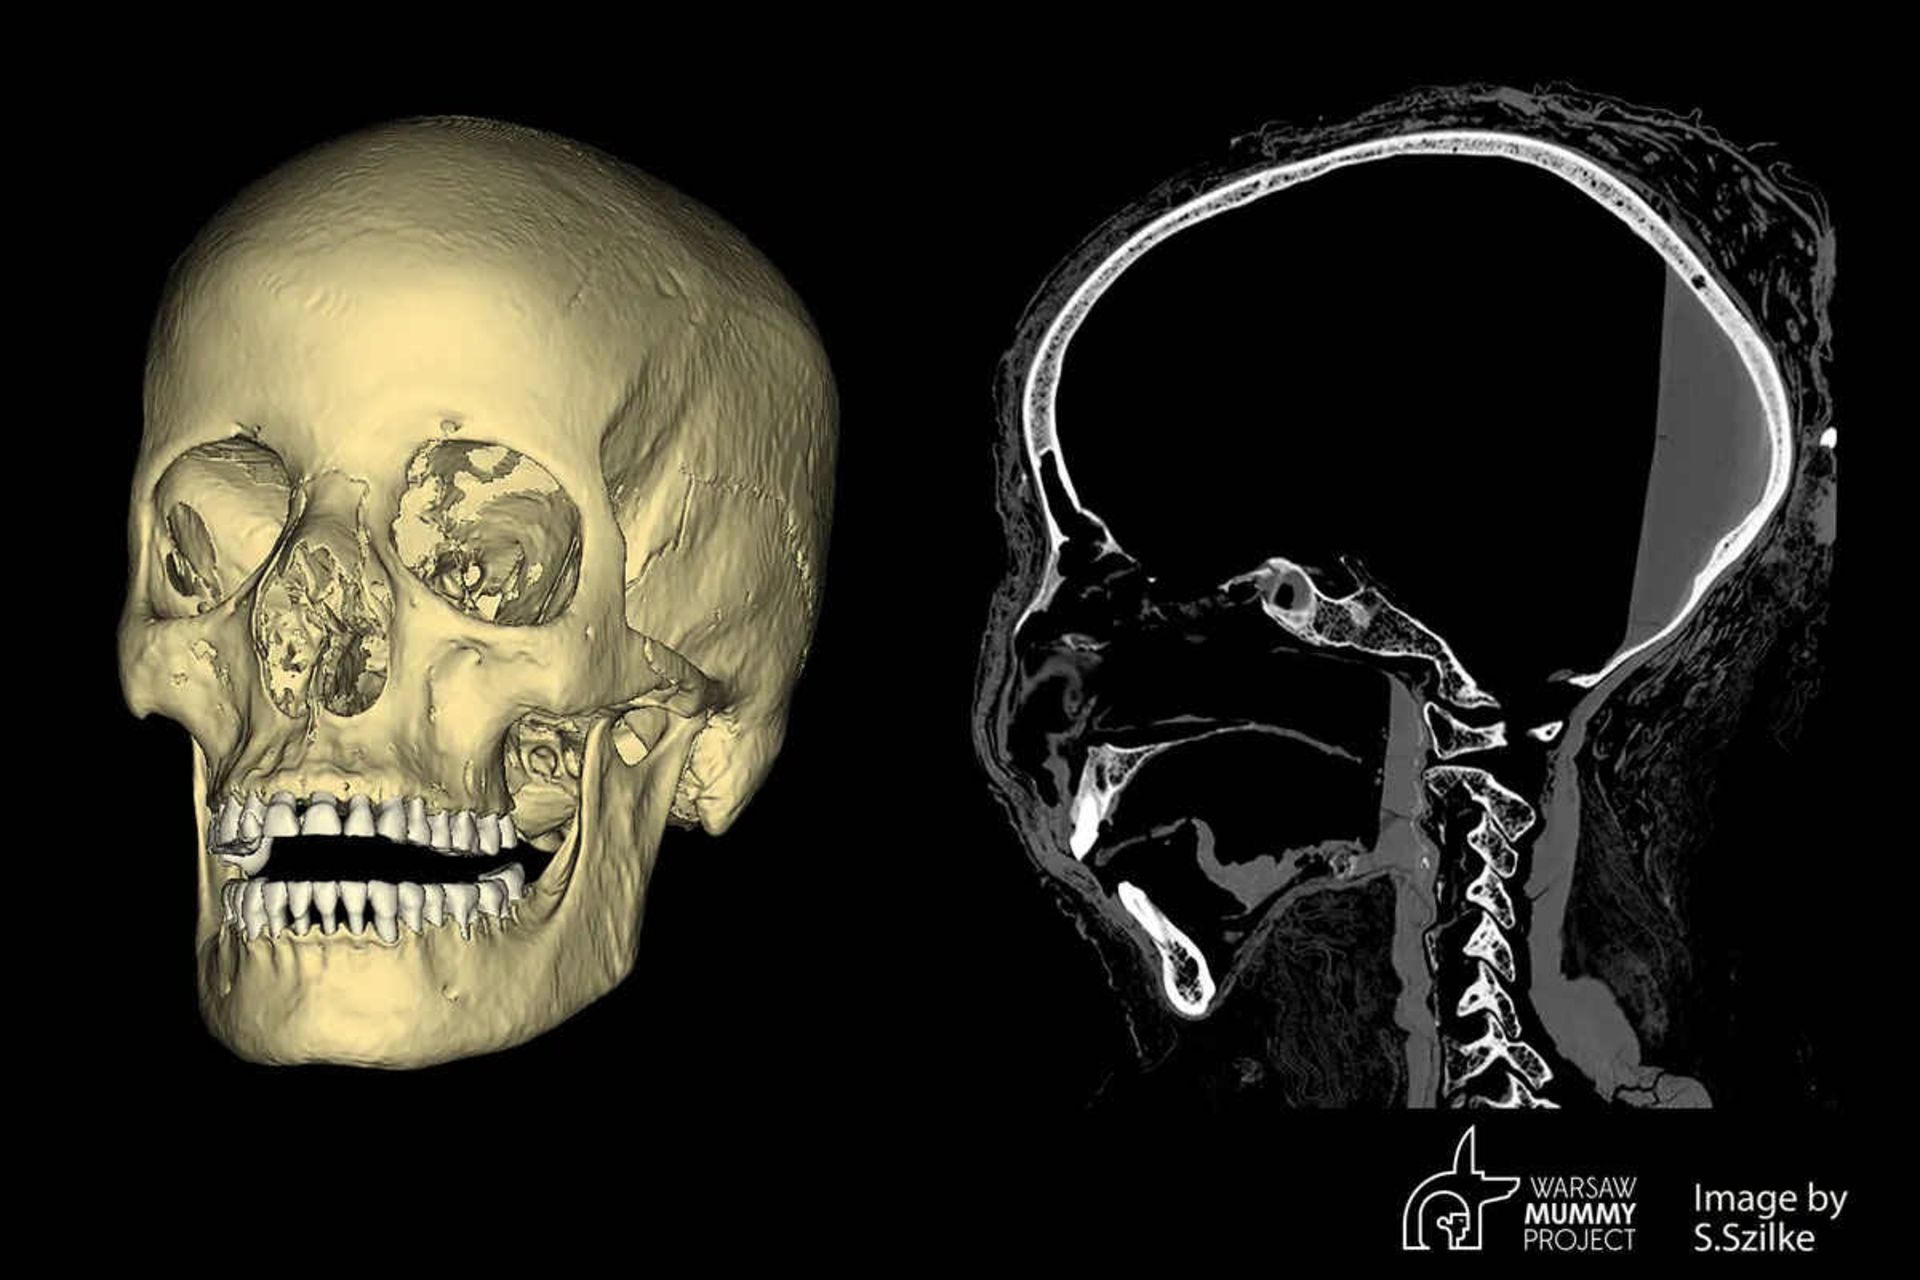

جمجمه مومیایی ۲۰۰۰ ساله مصری

جمجمه مومیایی ۲۰۰۰ ساله مصری.

محققان در اوایل سال ۲۰۲۲ با عکس‌برداری سی‌تی‌اسکن شواهد بیشتری از بانوی اسرارآمیز به دست آوردند و حتی از وجود جنین در حفره‌ی لگن این زن پرده برداشتند. مهم‌تر از همه اینکه یافته‌ها حاکی از آن بود که جنین درون رحم زن به دلیل قرار گرفتن در یک محیط بسیار اسیدی با اکسیژن پایین (مشابه آنچه در ترشی‌ها دیده می‌شود) در حالت کاملاً دست‌نخورده‌ای حفظ شده است.

اعضای پروژه مومیایی ورشو در ادامه تحقیقات خود تصمیم گرفتند علت مرگ این زن باستانی را کشف کنند. عکس‌برداری‌ها از جمجمه مومیایی باردار علائم غیرعادی را در این استخوان آشکار کرد. در واقع، آنچه محققان یافته بودند، نشان می‌داد این زن به سرطان مبتلا بوده است.